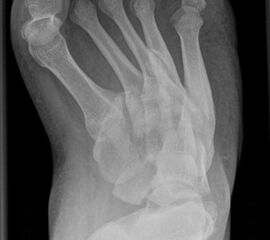

• Fuß belastet dp und seitlich (Abb. 14 und 15)

• Saltzman view (Abb. 16)

Zum Lesen der Bildbeschreibung und zur Vollansicht bitte die Bilder anklicken. Bilder: A. Simon

Typische Merkmale der Standard-dp-Röntgenaufnahme des Fußes im Stand

• Talus und Calcaneus verlaufen fast parallel

• Os naviculare ist gegenüber dem Talus nach medial gedrängt

• Metatarsalia überlappen sich basisnah

• Metatarsale I erscheint verkürzt

• Metatarsus adductus